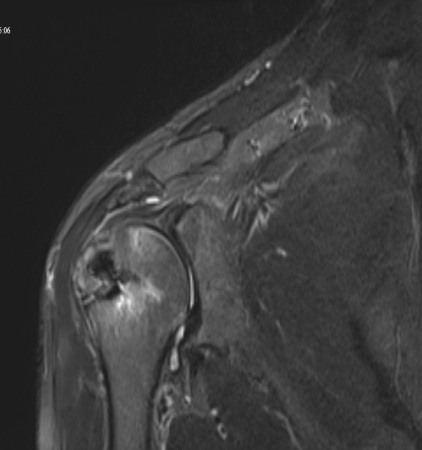

Preoperatif omuz MRI

Preoperatif omuz MRI — masif yırtık